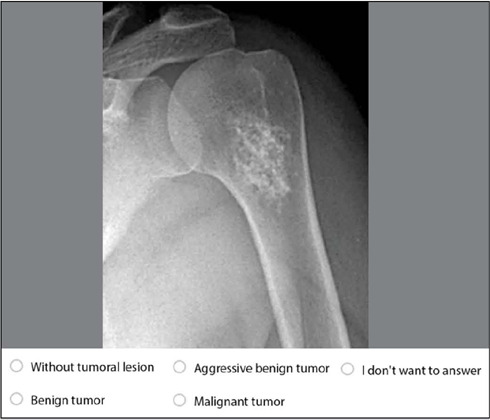

Objective: The objective was to assess the capability of non-specialist orthopedists in identifying bone lesions suggestive of tumors and thus classify them by employing a questionnaire with radiographs and comparison with specialists. We aim to gain an in-depth understanding of their diagnostic competence and provide insights into teaching the subject in orthopedic residency programs.

Methods: The sample consisted of 90 participants who answered the questionnaire: 18 orthopedic oncology specialists, 58 non-specialist orthopedists, and 14 orthopedic residents.

Results: Specialists achieved an average accuracy of 12.50 ± 1.07, while non-specialists scored 10.00 ± 0.60 (p<0.001). Among non-specialists, there was no statistical significance when comparing whether they underwent specialization internship during residency nor the duration of the year of such training. The period since graduation also indicated no differences.